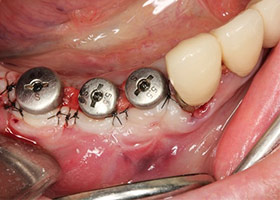

![proimages/case/Artificial_implant/HON07-1.jpg proimages/case/Artificial_implant/HON07-1.jpg]()

12.完成一階段式手術。